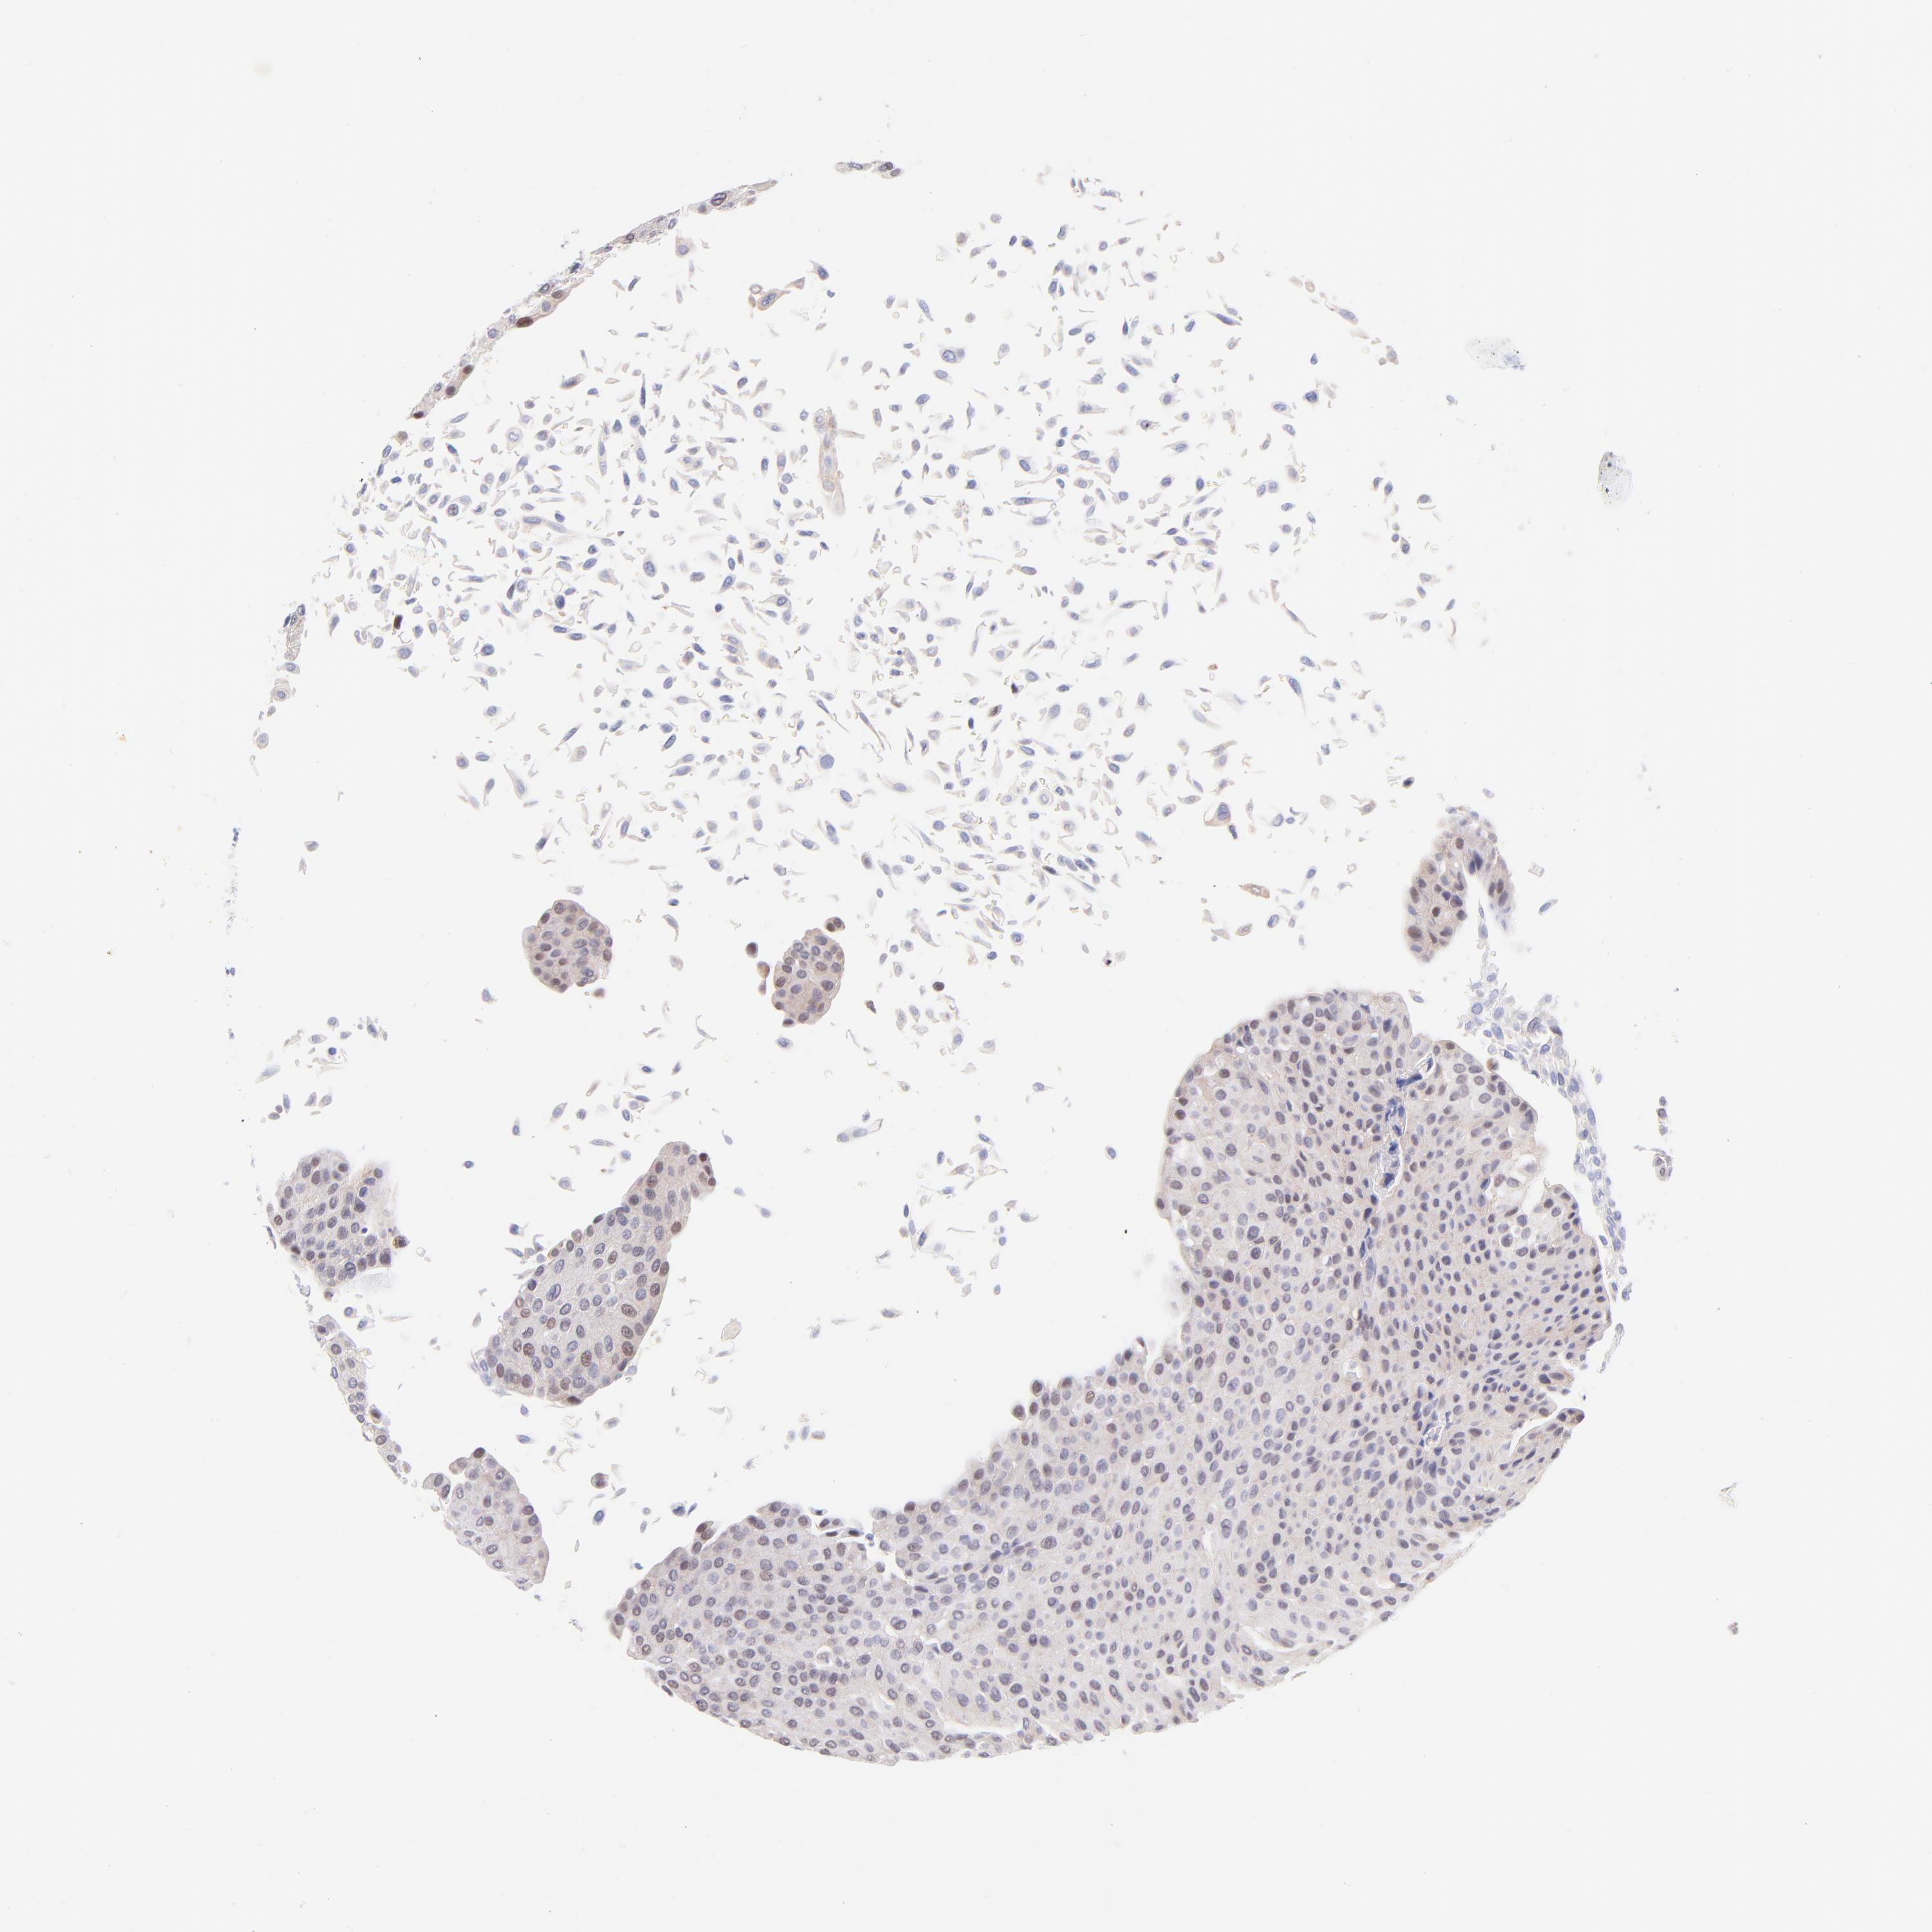

UROTHELIAL CANCER - Protein expressioni

A mouse-over function shows sample information and annotation data. Click on an image to view it in a full screen mode. Samples can be filtered based on level of antibody staining by selecting one or several of the following categories: high, medium, low and not detected. The assay and annotation is described here.

Antibody stainingi

Antibody staining in the annotated cell types in the current human tissue is reported as not detected, low, medium, or high, based on conventional immunohistochemistry profiling in selected tissues. This score is based on the combination of the staining intensity and fraction of stained cells.

Each image is clickable and will lead to virtual microscopy that enables deeper exploration of all samples and also displays staining intensity scores, fraction scores and subcellular localization as well as patient and tissue information for each sample.

Antibody HPA003155

Staining

High

Medium

Low

Not detected

Intensity

Strong

Moderate

Weak

Negative

Quantity

>75%

75%-25%

<25%

None

Location

Nuclear

Cytoplasmic/membranous

Cytoplasmic/membranous,nuclear

Urothelial carcinoma, Low grade